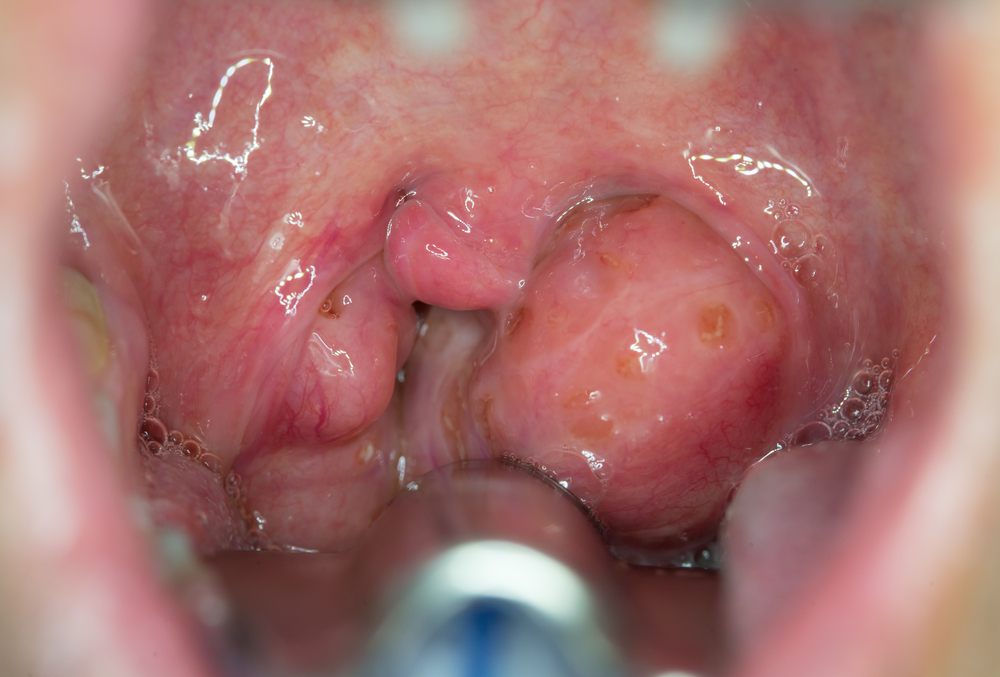

تُجرى لعلاج التهابات اللوزتين المتكررة أو تضخمهما المفرط، وهي من أكثر العمليات شيوعًا عند الأطفال.

استئصال اللحمية (Adenoidectomy)

خراجات اللوزتين أو الحلق (Peritonsillar Abscess drainage)